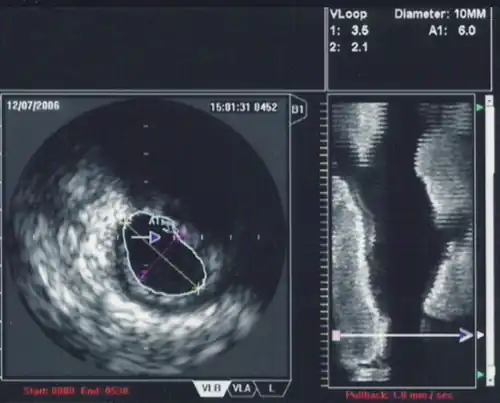

An IVUS image of the ostial left main coronary artery (left). The blue outline delineates the cross-sectional area of the lumen of the artery (A1 in the upper right corner), measuring 6.0 mm2. A two-dimensional mapping of the proximal LAD and left main coronary arteries is shown on the right.

While the routine use of IVUS during percutaneous coronary intervention does not improve short term outcomes,[10] there are a number of situations in which IVUS is of particular use in the treatment of coronary artery disease of the heart. In particular in cases when the degree of stenosis of a coronary artery is unclear, IVUS can directly quantify the percentage of stenosis and give insight into the anatomy of the plaque.

One particular use of IVUS in the coronary anatomy is in the quantification of left main disease in cases where routine coronary angiography gives equivocal results. Many studies in the past have shown that significant left main disease can increase mortality,[11] and that intervention (either coronary artery bypass graft surgery or percutaneous coronary intervention) to reduce mortality is necessary when the left main stenosis is significant.

When using IVUS to determine whether an individual's left main disease is clinically significant, in terms of the desirability of physical intervention, the two most widely used parameters are the degree of stenosis and the minimal lumen area.[12] A cross sectional area of ≤7 mm² in a symptomatic individual or ≤6 mm² in an asymptomatic individual[13] is considered to be clinically significant and warrants intervention to improve one-year mortality. However, these exact cutoffs are up for debate and different cutoff cross-sectional areas may be used in practice depending on differing interpretations of the trial data.